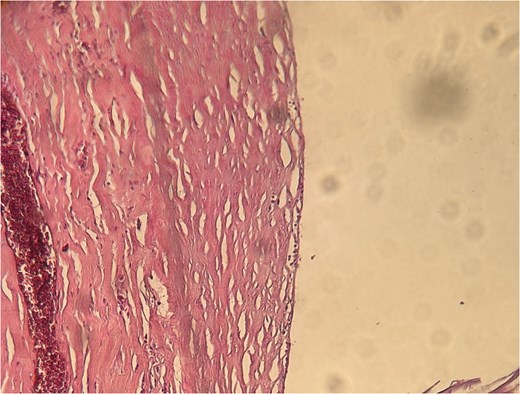

A 54-year-old Moroccan male with no significant medical history presented with chronic left iliac fossa pain lasting several months, without associated digestive or systemic symptoms, and preserved general condition. Clinical examination revealed left iliac fossa tenderness. Abdominopelvic ultrasound suggested a cystic mass in the left iliac fossa, confirmed by CT scan, which identified a cystic lesion in the colonic mesentery measuring 35 mm. Surgical exploration revealed a cystic mass in the colonic mesentery, which was completely excised. Histopathological examination showed variable-sized lymphatic cystic cavities containing eosinophilic material (Fig. 6). The patient’s postoperative course was uneventful.

Histopathological findings of lymphatic cystic cavities with eosinophilic content.